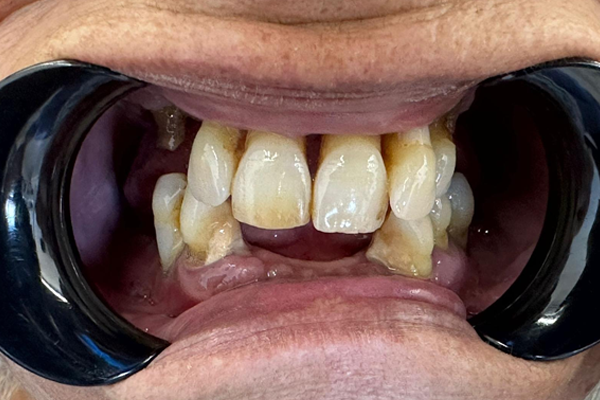

Conoce el antes y después de nuestros tratamientos